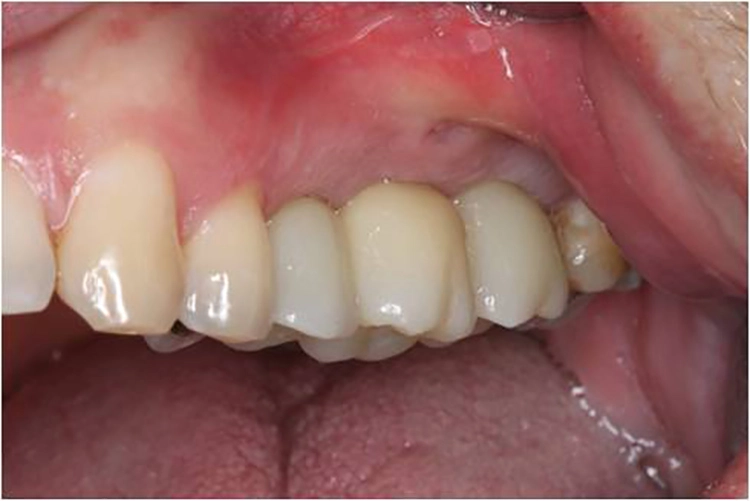

Aufgrund der Augmentation erfolgte die Freilegung 5 Monate postoperativ. Nach Ausformung des Emergenzprofils (Abb. 4i) erfolgte die definitive prothetische Versorgung durch eine okklusal verschraubte Einzelkrone (Abb. 4j).